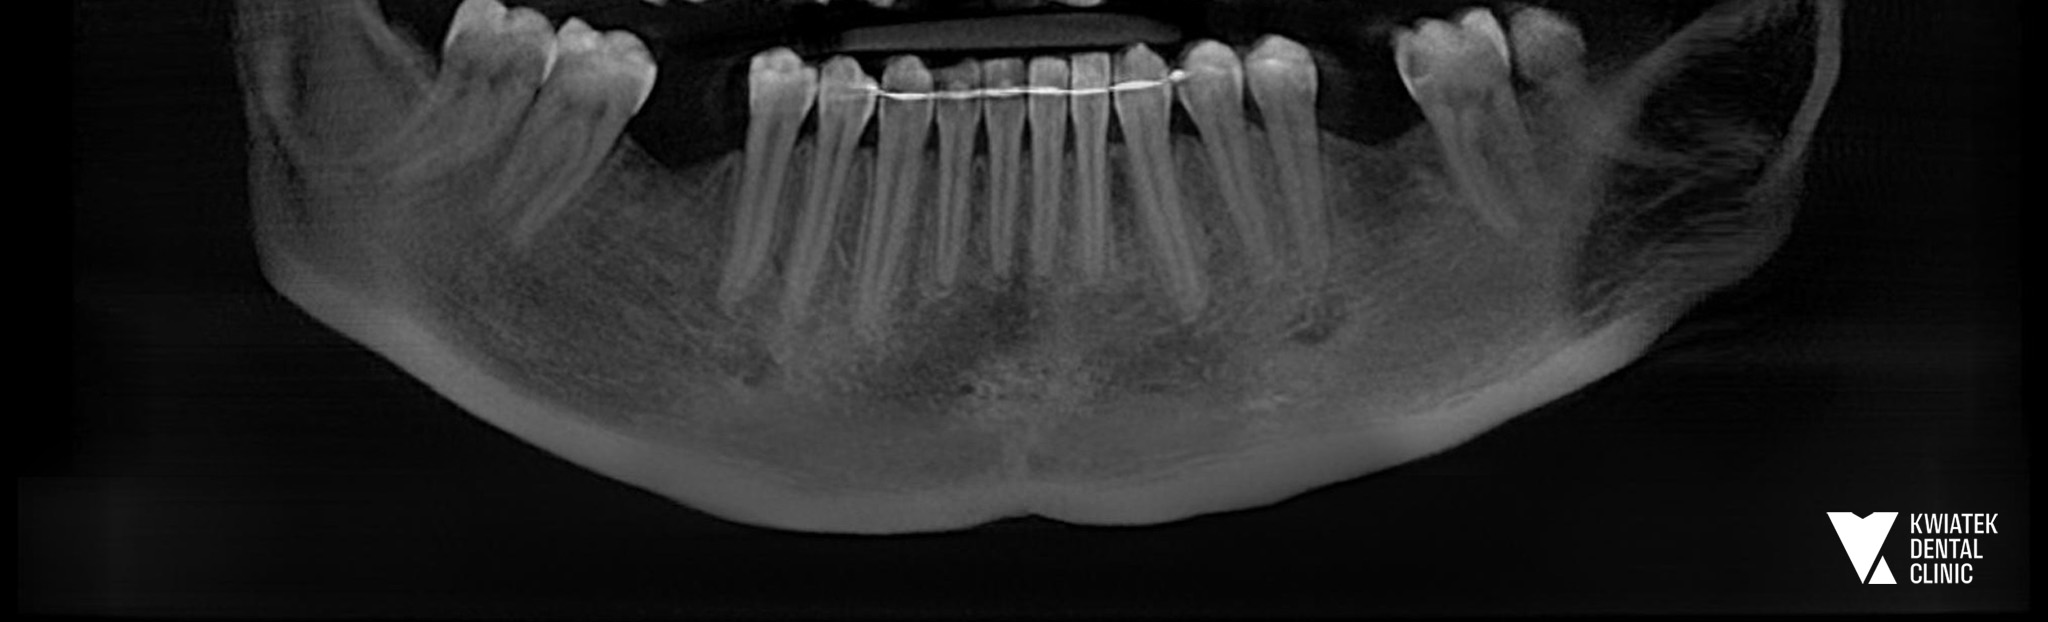

PRZED

Pacjentka zgłosiła się do naszej kliniki z problemem braków zębowych w odcinkach bocznych żuchwy. Braki te dotyczyły pierwszych zębów trzonowych, czyli tzw. zębów szóstych. Warto podkreślić, że to właśnie one najczęściej są tracone jako pierwsze. Wynika to z faktu, że są pierwszymi stałymi zębami trzonowymi pojawiającymi się w jamie ustnej, zwykle już około szóstego roku życia, przez co przez wiele lat poddawane są największym obciążeniom podczas żucia.

Długotrwały brak zębów w tej okolicy może prowadzić do zaburzeń zgryzu, przeciążenia pozostałych zębów oraz stopniowej utraty kości. Dlatego tak ważne jest przywrócenie pełnej funkcji uzębienia w sposób trwały i biologicznie bezpieczny.

Proces leczenia rozpoczął się od szczegółowej diagnostyki stomatologicznej oraz analizy stanu jamy ustnej. Wykonano badania radiologiczne, dokumentację fotograficzną oraz skan wewnątrzustny, który umożliwił cyfrowe zaplanowanie leczenia implantologicznego.

Na podstawie diagnostyki stwierdzono brak zębów 36 oraz 46 w żuchwie. Już wcześniej, podczas wcześniejszych wizyt, zaproponowano Pacjentce odbudowę tych braków przy użyciu implantów, jako najbardziej przewidywalnej i trwałej metody leczenia.